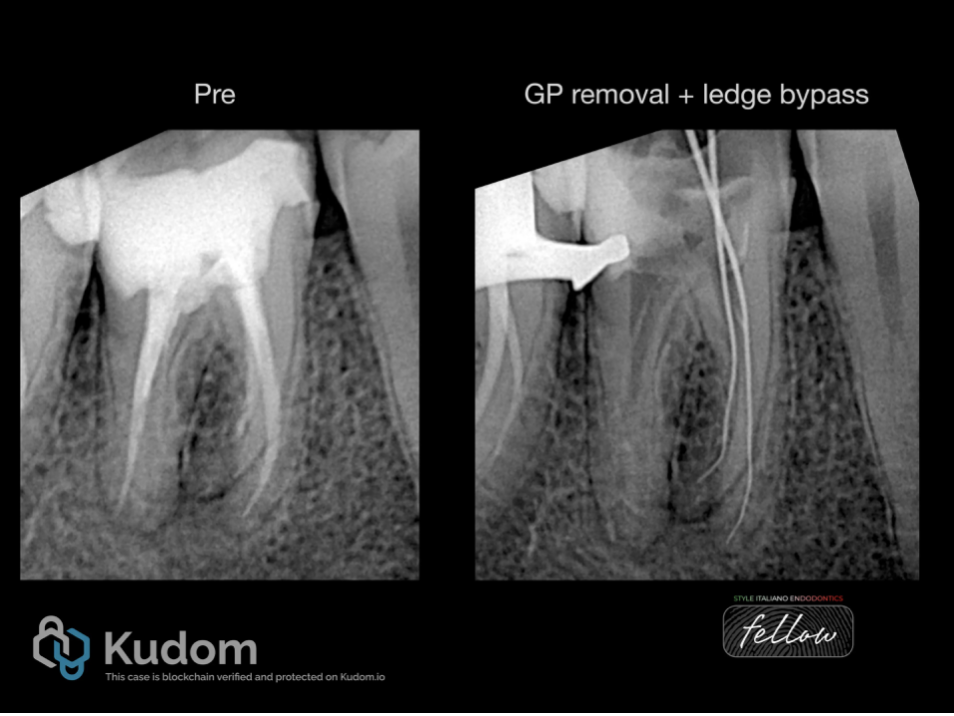

Fig. 5

Another lower first molar with shows a different anatomical variation with (RP) . The tooth previously improperly treated with short obturation and missed DL canal leading to periapical periodontitis.

Fig. 6

After removing the old root canal filling and ledge bypass in the (RP) , A proper shaping and cleaning performed and cone fit x-ray image taken.